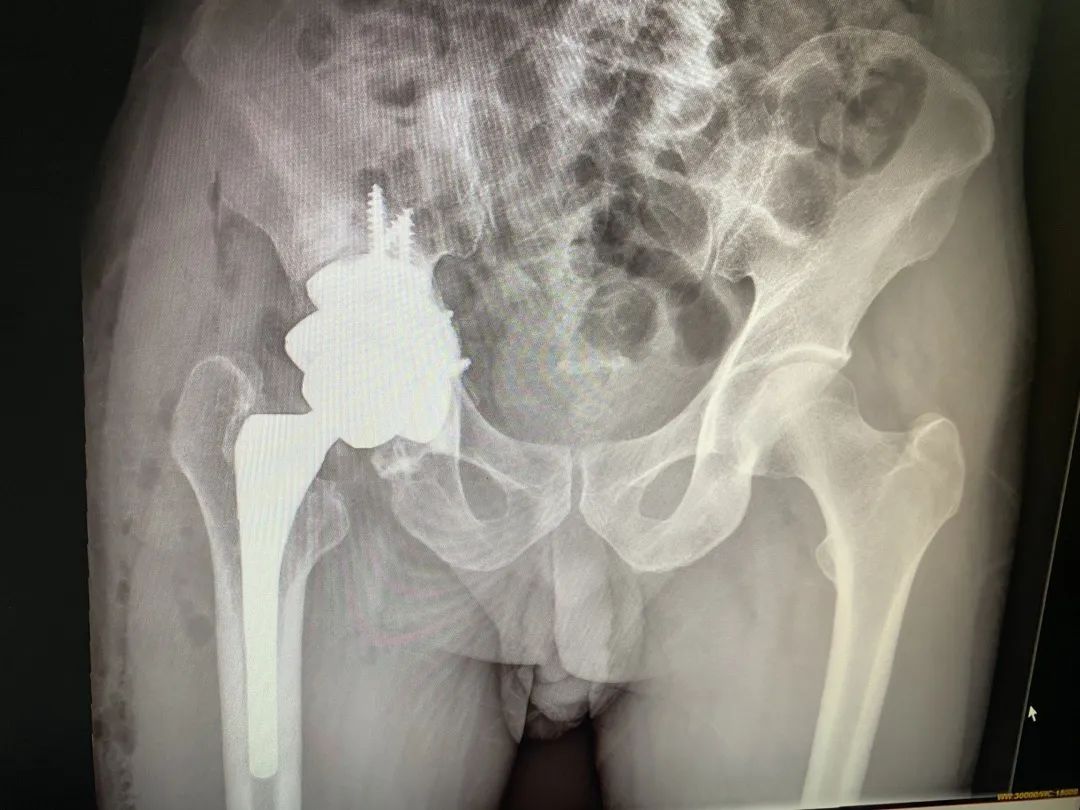

经过充分的术前准备,实施了复杂人工髋关节翻修术。手术按照术前规划顺利完成。术后,蒋大爷恢复理想。

术后

李大爷同法给予手术,效果理想。

术前